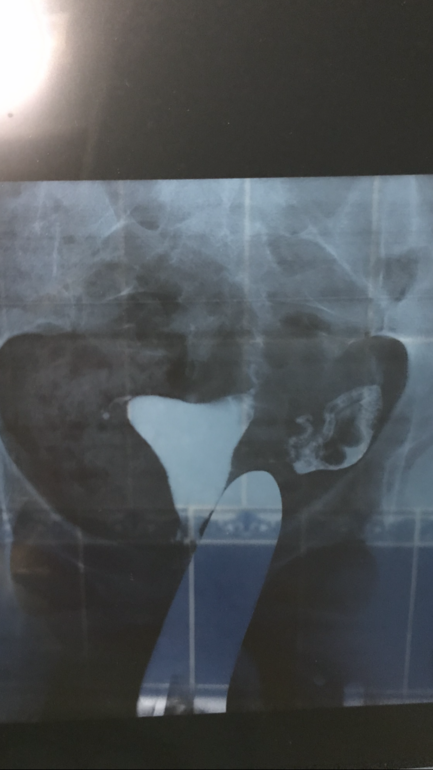

Можно с такими снимками планировать?

В том: что как вы думаете есть ли шансы забеременеть с такой трубой? ( глядя на снимки) или там совсем все плохо?

Ну мне с телефона плохо видно, но жидкость трубу прошла. Как уж она ее проходила, может не сразу... Но в целом, картина спаечного процесса вроде вырисовывается.

А как понять где спаечный процесс? Где он прорисовывается?( в чем это выражено? Объясните мне пожалуйста 🙏🏼Хочу понять

Это вот в конце трубы где? Где якобы жидкость вышла? Там да

Там где жидкость скопилась, там спайки. В идеале, жидкость должна свободно растечься по брюшине.

Спайки же могут быть где угодно и различные, если есть на выходе из трубы, то с большой долей вероятности, есть и в ней самой (возможно жидкостью пробили, такое бывает часто).

Нет, в брюшной полости не мешают, если не распространяются на область труб и яичников. У Вас видимо спаяна труба на выходе была и спаечный процесс в прилегающих тканях. Ну и потому и жидкость не растеклась как положено, а скопилась в одном месте. А мешает ли такое зачатию, кто ж скажет...в целом, труба извилиста, но проходима, пробуйте.

Ну и конечно Ваши страхи понятны. Тем более, судя по снимку, у Вас одной трубы уже нет.

Вот у меня по трубе спокойно прошло врач сказала. А потом в конце встала в трубе

Потом врач под давлением больше жидкости пустила и видимо пробила🤷🏼♀️

Есть ли шансы с такой трубой-я вот про что🤷🏼♀️

Есть шансы, потому что она у вас судя по снимку проходима. А что написано в заключении?